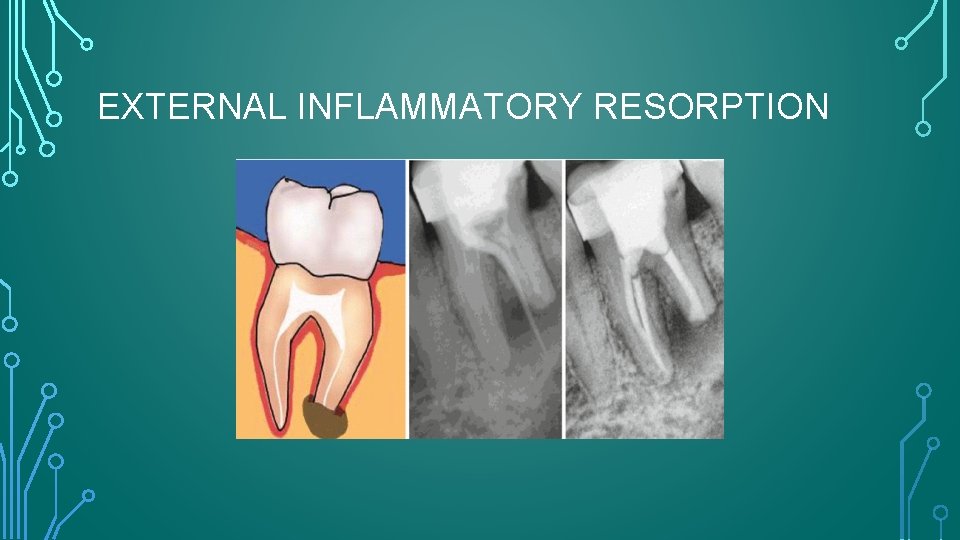

EXTERNAL INFLAMMATORY RESORPTION

RADIOGRAPHIC FEATURES • Radiolucent , concave and sometimes ragged bowl shaped excavations • Associated radiolucency in the adjacent alveolar bone. • Complete loss of the lamina dura. • Can be seen as early as 3 - 4 weeks after traumatic dental injuries, and if it will develop , EIR always seen within 1 year after the injury. • Can have rapid onset and aggressive progression, such that complete resorption can occur within 3 months.